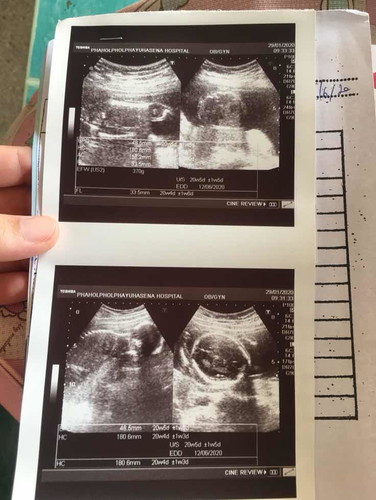

20w5dหมอบอกเพศยังไม่ชัดแต่บอกผู้ชายแต่ไม่100%แม่ๆๆท่านไหนพอดูเพศน้องออกมั้งค่ะ

ในใบซาวไม่เห็นท่าที่เห็นเพศน้องเลยค่ะ